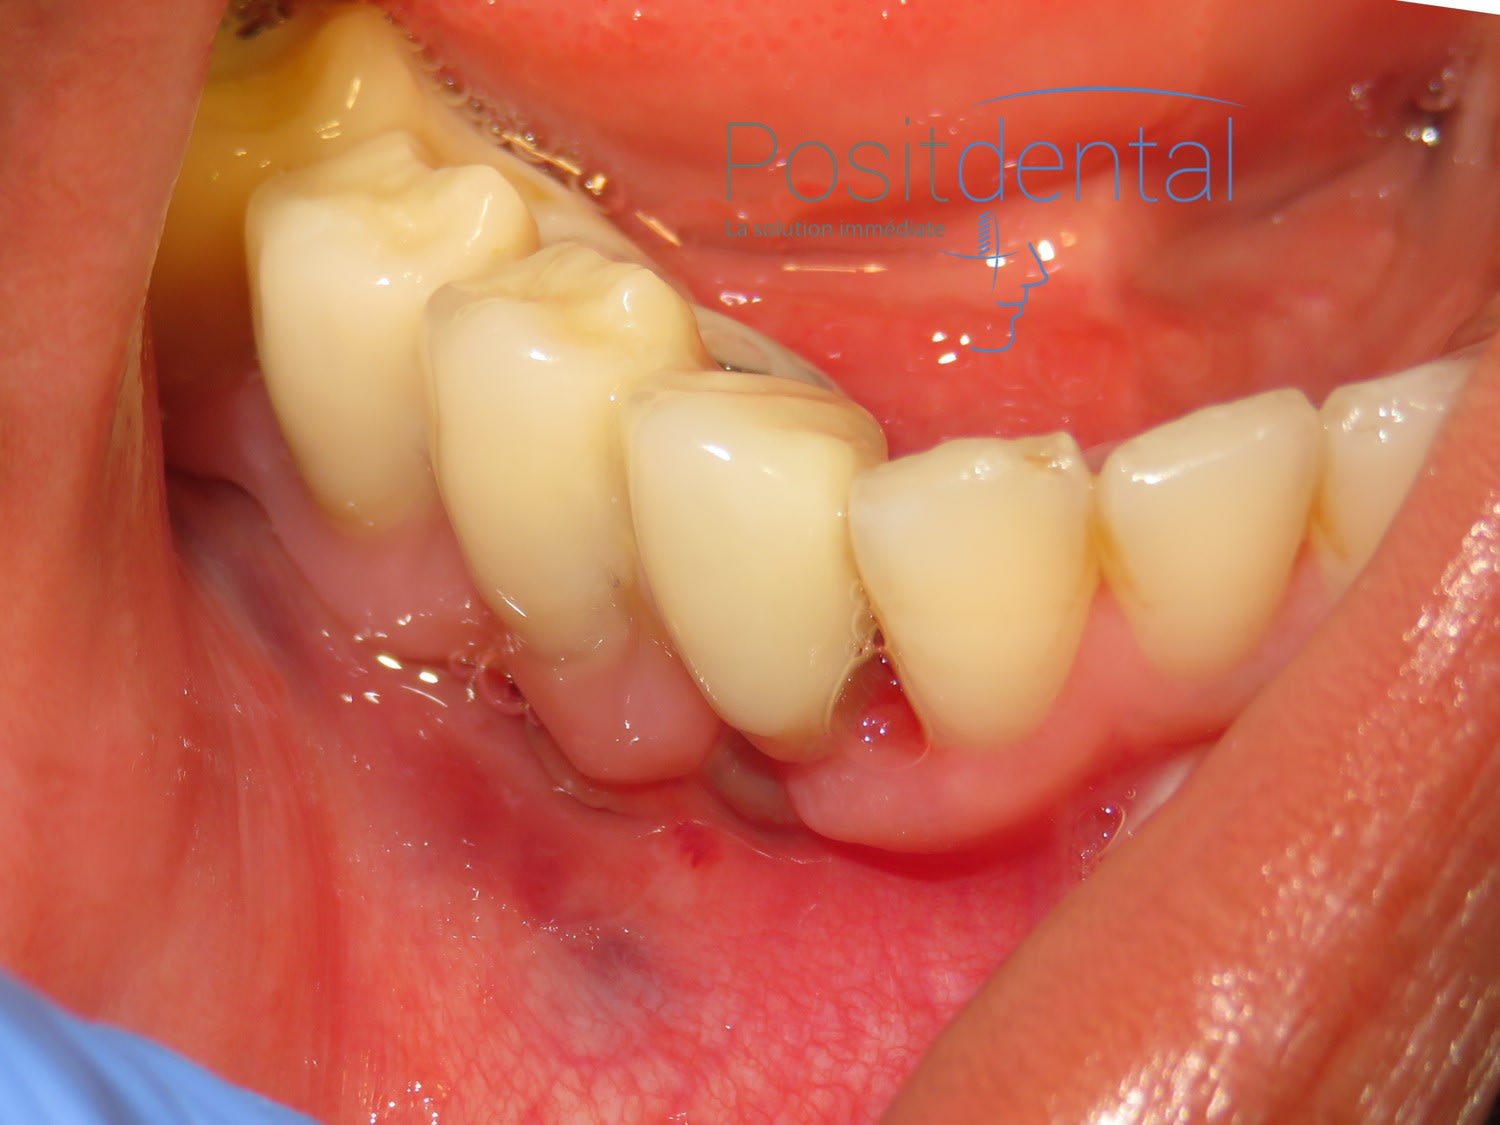

patiente en fin d'intervention

non, comme ça!